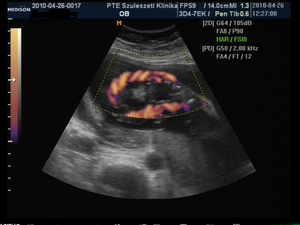

meg én a magam alig 19 hetével nem szólok bele